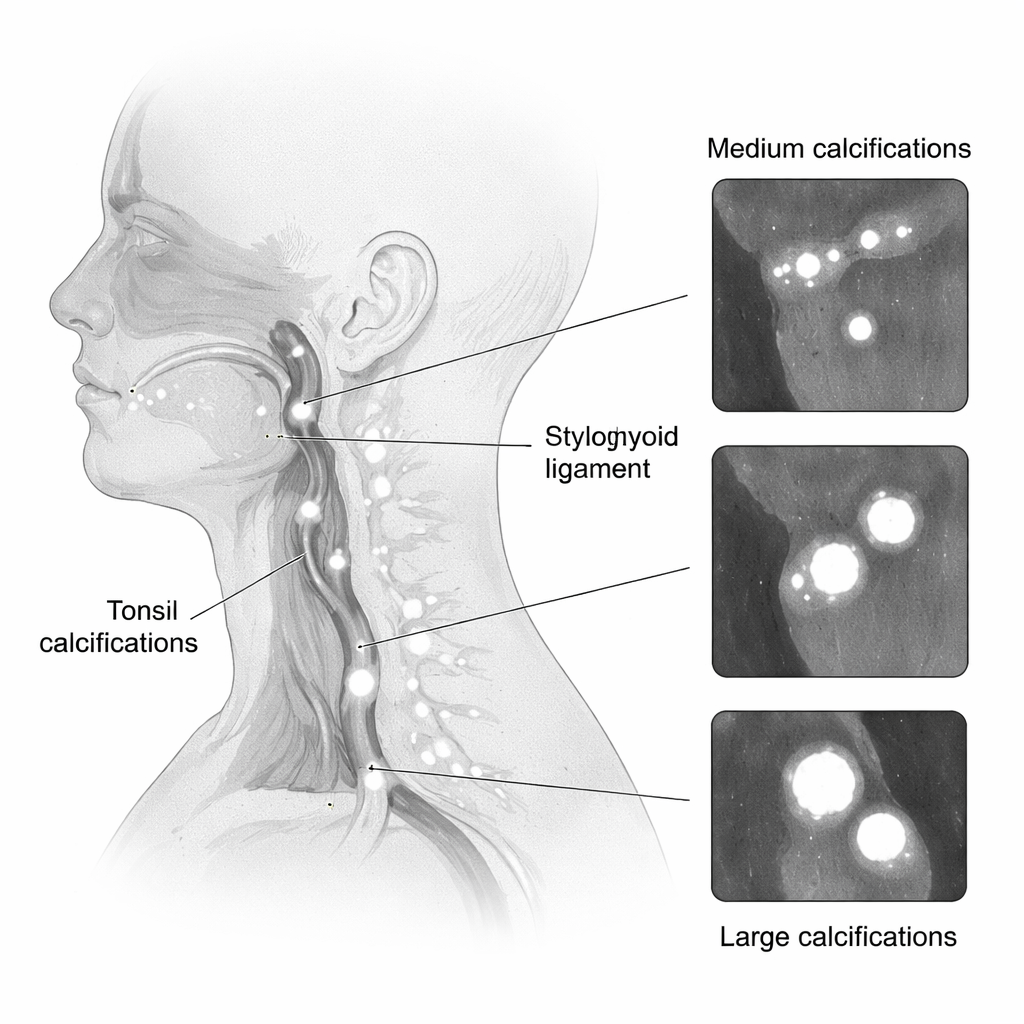

Quando i dentisti richiedono una tomografia computerizzata cone-beam (CBCT), di solito si concentrano su una piccola regione delle ossa mascellari per pianificare impianti, trovare denti inclusi o valutare la perdita ossea. Ma la scansione cattura anche i tessuti molli vicini, comprese le tonsille, i vasi del collo e i legamenti. I ricercatori si sono posti una domanda pratica: se una scansione è mirata principalmente alla mascella superiore (mascella) o inferiore (mandibola), quanto è probabile che mostri queste calcificazioni nascoste e questo cambia con l’età o il sesso del paziente? Rispondere a questo potrebbe aiutare i radiologi a sapere dove guardare con maggiore attenzione e quali pazienti potrebbero beneficiare di un follow-up medico.

Il team ha riesaminato 420 scansioni CBCT eseguite tra il 2020 e il 2024 in una clinica odontoiatrica universitaria in Iran. Ogni scansione copriva o la mascella superiore o la mandibola utilizzando un campo visivo standardizzato. I pazienti avevano un’età compresa tra 6 e 82 anni. Sono state escluse le scansioni di scarsa qualità e quelle distorte da interventi chirurgici o da rare patologie calcificanti. Due radiologi esperti, addestrati in precedenza su casi di esempio, hanno controllato indipendentemente ogni scansione per tipi specifici di calcificazioni dei tessuti molli, come i tonsilloliti, i legamenti stiloiodei calcificati, i calcoli salivari, i linfonodi calcificati e, nelle scansioni della mandibola, depositi calcificati nelle arterie carotidi del collo. Hanno misurato la dimensione maggiore di ogni reperto e li hanno raggruppati come piccoli (1 millimetro o meno), medi (1–3 millimetri) o grandi (3 millimetri o più). L'accordo tra i lettori è stato quasi perfetto, il che significa che i reperti erano altamente affidabili.

Le calcificazioni dei tessuti molli erano comuni. Complessivamente, erano circa 1,3 volte più probabili nelle scansioni focalizzate sulla mandibola rispetto a quelle mirate alla mascella. In entrambe le regioni, i tonsilloliti erano il tipo più frequente, seguiti dai legamenti stiloiodei calcificati. Nelle scansioni della mandibola, circa un paziente su tre presentava tonsilloliti, mentre nelle scansioni della mascella quasi uno su cinque li aveva. La maggior parte dei depositi, inclusi i tonsilloliti e i legamenti calcificati, rientrava nella categoria di dimensione “media”, abbastanza grandi da essere chiaramente visibili sulla CBCT ma spesso ancora inosservati nella vita quotidiana.

L’età è risultata essere un forte predittore. Con l’avanzare dell’età, le calcificazioni non solo comparivano più frequentemente ma tendevano anche a essere più grandi. Le persone sopra i 50 anni avevano più del doppio delle probabilità di avere tonsilloliti ed erano molto più propense a mostrare placche calcificate nell’area carotidea nelle scansioni della mandibola. Nelle scansioni della mascella, grandi legamenti calcificati erano molto più comuni dopo i primi quarant’anni. Sono emersi anche alcuni schemi legati al sesso: nel campo della mascella, le donne mostravano più spesso legamenti stiloiodei calcificati, mentre negli uomini erano più frequenti calcificazioni a livello cutaneo. Tuttavia, molti tipi di calcificazione erano troppo rari per trarre conclusioni solide sulle differenze legate al sesso. Gli autori sottolineano che le scansioni della mandibola, in particolare, catturano regioni vicine alla gola e ai vasi del collo, rendendole particolarmente preziose per individuare tonsilloliti e possibili calcificazioni arteriose.

Trasformare reperti incidentali in segnali di allarme precoce